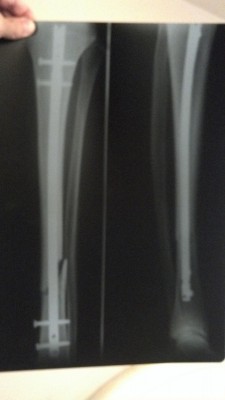

Está aí o resultado de acelerar em terreno irregular

Mas estou bem, três meses de molho!

Olha ai a minha foto depois do Enduro Fim da Fazenda.

Tibia, fratura, haste, parafusos,

Já são 2,5 meses de molho.

Vc não ta sozinho. kkkkkkkkkkk